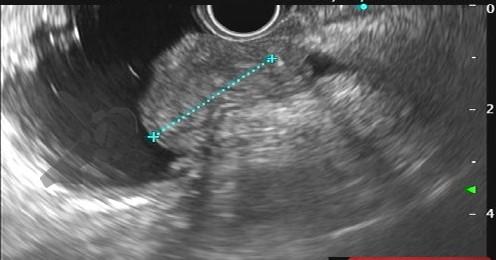

Figuras 1 e 2. Imagem endoscópica em visão direta de lesão protrusa entre pequena curvatura e parede posterior de corpo gástrico proximal, revestida por mucosa com superfície regular, normocorada e íntegra. A imagem ecoendoscópica demonstra lesão com ecogenicidade hipoecoica, ecotextura homogênea, formato ovalado, sem características internas, sem vascularização ao doppler, limites precisos, contornos regulares, medindo aproximadamente 20 x 6 mm e inserida em camada muscular própria. Punções ecoguiadas foram realizadas com agulha FNB, sendo o anatomopatológico e imuno-histoquímica compatíveis com GIST gástrico. Fonte: arquivos do Instituto do Câncer do Estado de São Paulo (ICESP/HCFMUSP)Figuras 1 e 2. Imagem endoscópica em visão direta de lesão protrusa entre pequena curvatura e parede posterior de corpo gástrico proximal, revestida por mucosa com superfície regular, normocorada e íntegra. A imagem ecoendoscópica demonstra lesão com ecogenicidade hipoecoica, ecotextura homogênea, formato ovalado, sem características internas, sem vascularização ao doppler, limites precisos, contornos regulares, medindo aproximadamente 20 x 6 mm e inserida em camada muscular própria. Punções ecoguiadas foram realizadas com agulha FNB, sendo o anatomopatológico e imuno-histoquímica compatíveis com GIST gástrico. Fonte: arquivos do Instituto do Câncer do Estado de São Paulo (ICESP/HCFMUSP)Figuras 3 e 4. Imagem endoscópica em visão direta de abaulamento de parede em segunda porção duodenal distalmente à papila duodenal maior, revestida por mucosa com íntegra, de coloração amarelada e superfície regular. A ecoendoscopia demonstra lesão com ecogenicidade hiperecoica, ecotextura homogênea, formato arredondado, medindo cerca de 10 mm no maior eixo, com limites precisos, contornos regulares, medindo cerca de 10 mm no maior diâmetro e inserida em camada submucosa, sendo os achados endoscópicos e ecoendoscópicos compatíveis com lipoma.Figuras 3 e 4. Imagem endoscópica em visão direta de abaulamento de parede em segunda porção duodenal distalmente à papila duodenal maior, revestida por mucosa com íntegra, de coloração amarelada e superfície regular. A ecoendoscopia demonstra lesão com ecogenicidade hiperecoica, ecotextura homogênea, formato arredondado, medindo cerca de 10 mm no maior eixo, com limites precisos, contornos regulares, medindo cerca de 10 mm no maior diâmetro e inserida em camada submucosa, sendo os achados endoscópicos e ecoendoscópicos compatíveis com lipoma.Fig. 5. Imagem endoscópica em visão direta de lesão protrusa em parede anterior de antro gástrico proximal, revestida por mucosa normocorada, com superfície regular, sendo sugestiva de lesão subepitelial.Fig. 6. A ecoendoscopia evidencia lesão com ecogenicidade hipoecoica, ecotextura predominantemente homogênea, formato arredondado, limites precisos, bordos regulares, medindo aproximadamente 13,4 x 12 mm, sem focos hiperecoicos ou calcificações no interior e inserida na camada muscular própria. Punções ecoguiadas foram realizadas com agulha FNB, sendo anatomopatológico e imuno-histoquímica confirmando schwanomma gástrico.Fig. 7 e 8. Imagem de esofagogastroduodenoscopia demonstra lesão protrusa em papila duodenal maior revestida por mucosa enantemática e com superfície com três erosões recobertas por fibrina.Fig. 7 e 8. Imagem de esofagogastroduodenoscopia demonstra lesão protrusa em papila duodenal maior revestida por mucosa enantemática e com superfície com três erosões recobertas por fibrina.Fig. 9 e 10. Imagem à ecoendoscopia demonstra lesão com formato ovalado, ecogenicidade hipoecoica, ecotextura heterogênea, com contornos regulares, sem adenopatia adjacente, sem vascularização ao doppler, sem características internas, medindo cerca de 20 x 11 x 24 mm, inserida na camada submucosa, não havendo acometimento da muscular própria. Foram realizadas punções ecoguiadas com agulha FNA 22 gauge, sendo o anatomopatológico e imunohistoquímica compatíveis com tumor neuroendócrino de papila duodenal bem diferenciado grau 1.Fig. 9 e 10. Imagem à ecoendoscopia demonstra lesão com formato ovalado, ecogenicidade hipoecoica, ecotextura heterogênea, com contornos regulares, sem adenopatia adjacente, sem vascularização ao doppler, sem características internas, medindo cerca de 20 x 11 x 24 mm, inserida na camada submucosa, não havendo acometimento da muscular própria. Foram realizadas punções ecoguiadas com agulha FNA 22 gauge, sendo o anatomopatológico e imunohistoquímica compatíveis com tumor neuroendócrino de papila duodenal bem diferenciado grau 1.Fig. 11 e 12. Esofagogastroduodenoscopia demonstra abaulamento de parede anterior de corpo gástrico proximal, com mucosa normocorada, superfície regular com depressão central, sendo compatível com lesão subepitelialFig. 11 e 12. Esofagogastroduodenoscopia demonstra abaulamento de parede anterior de corpo gástrico proximal, com mucosa normocorada, superfície regular com depressão central, sendo compatível com lesão subepitelialFig. 13 e 14. Ecoendoscopia demonstrou formação com ecogenicidade hipoecoica, ecotextura homogênea, formato ovalado, limites bem definidos, contornos regulares, medindo aproximadamente 13 mm e inserida na camada submucosa. Lesão foi submetida a ressecção endoscópica transmural com dispositivo FTRD. A histopatologia e imunohistoquímica confirmaram TNE gástrico bem diferenciado grau 2.Fig. 13 e 14. Ecoendoscopia demonstrou formação com ecogenicidade hipoecoica, ecotextura homogênea, formato ovalado, limites bem definidos, contornos regulares, medindo aproximadamente 13 mm e inserida na camada submucosa. Lesão foi submetida a ressecção endoscópica transmural com dispositivo FTRD. A histopatologia e imunohistoquímica confirmaram TNE gástrico bem diferenciado grau 2.